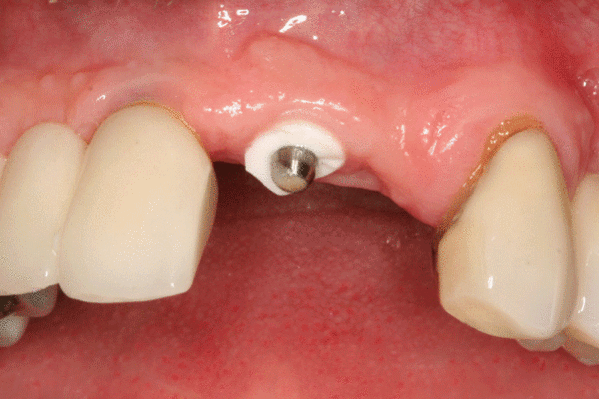

- формирователь десны (также: формирователь десневой манжеты, ФДМ; жарг. хилинг от англ. healing abutment досл. «опора для заживления; заживляющая опора»)

- абатмент (от англ. abutment досл. «опора») — прикрепляемая к имплантату часть конструкции, служит опорой для будущей коронки или протеза

Разборный имплантат состоит из непосредственно имплантата и надстройки (супраструктуры), именуемой абатментом. Такой имплантат может быть установлен по одно- и двухэтапному протоколу. Двухэтапный протокол подразумевает полное погружение имплантата и накрывание его слизистой оболочкой, в результате чего исключается любой контакт имплантата с полостью рта — эта процедура называется первым этапом дентальной имплантации. Второй этап заключается в установке какой-либо надстройки (супраструктуры) — это может быть как формирователь десны, так и абатмент с временной коронкой или другим видом протезной конструкции. После какого промежутка времени будет выполнен второй этап обычно решает имплантолог, опираясь на данные о качестве костной ткани, возраст и общее состояние пациента, а также свой клинический опыт. Классические сроки составляют 4—6 месяцев, однако последнее время существует тенденция к сокращению сроков ожидания до 2,5—3 месяцев. Это связано с лучшим пониманием процесса остеоинтеграции, а также оптимизацией макродизайна и микрохарактеристик поверхности имплантатов.

В неразборном имплантате (употребляются также термины: одноэтапный имплантат, моноимплантат) внутрикостная часть имплантата и абатмент обычно изготовлены из единого куска материала. После установки имплантат своей наддесневой частью сразу оказываются в контакте с полостью рта. На усмотрение доктора устанавливается формирователь десны либо временная коронка. В случае установки временной протезной конструкции (коронки, моста или полного протеза) на имплантат не позднее трёх дней после имплантации говорят о немедленной нагрузке.